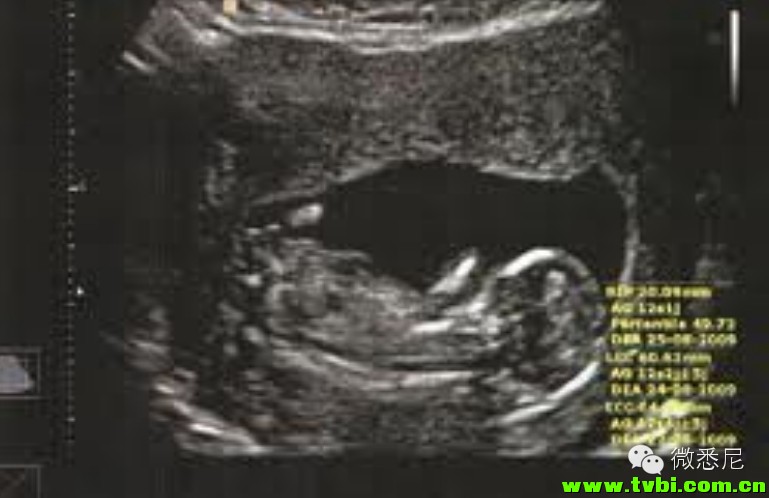

哦忘了说了,到了5个月的时候就可以知道baby的性别了,一般midwife在做B超时会问你想不想知道孩子是男是女,当然也有朋友遇到过奇葩的midwife,直接就告诉你“Your son is very good”,毫无惊喜感啊有木有!!太忧桑了。。。

上图是小S的B超,这一胎是个女娃娃。做B超的时候midwife会很热情地为产妇讲解哪里是宝宝的头、手和双腿。